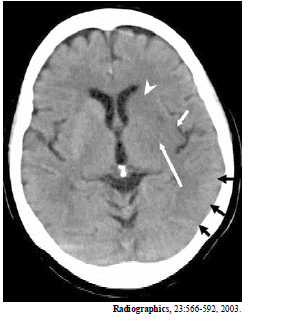

A imagem acima é de uma paciente de 65 anos de idade, com hemiplegia direita há cinco horas. Com base nessa imagem, é correto afirmar que

a cabeça de flexa indica o núcleo caudado.

as flechas negras indicam edema cortical no lobo occipital.